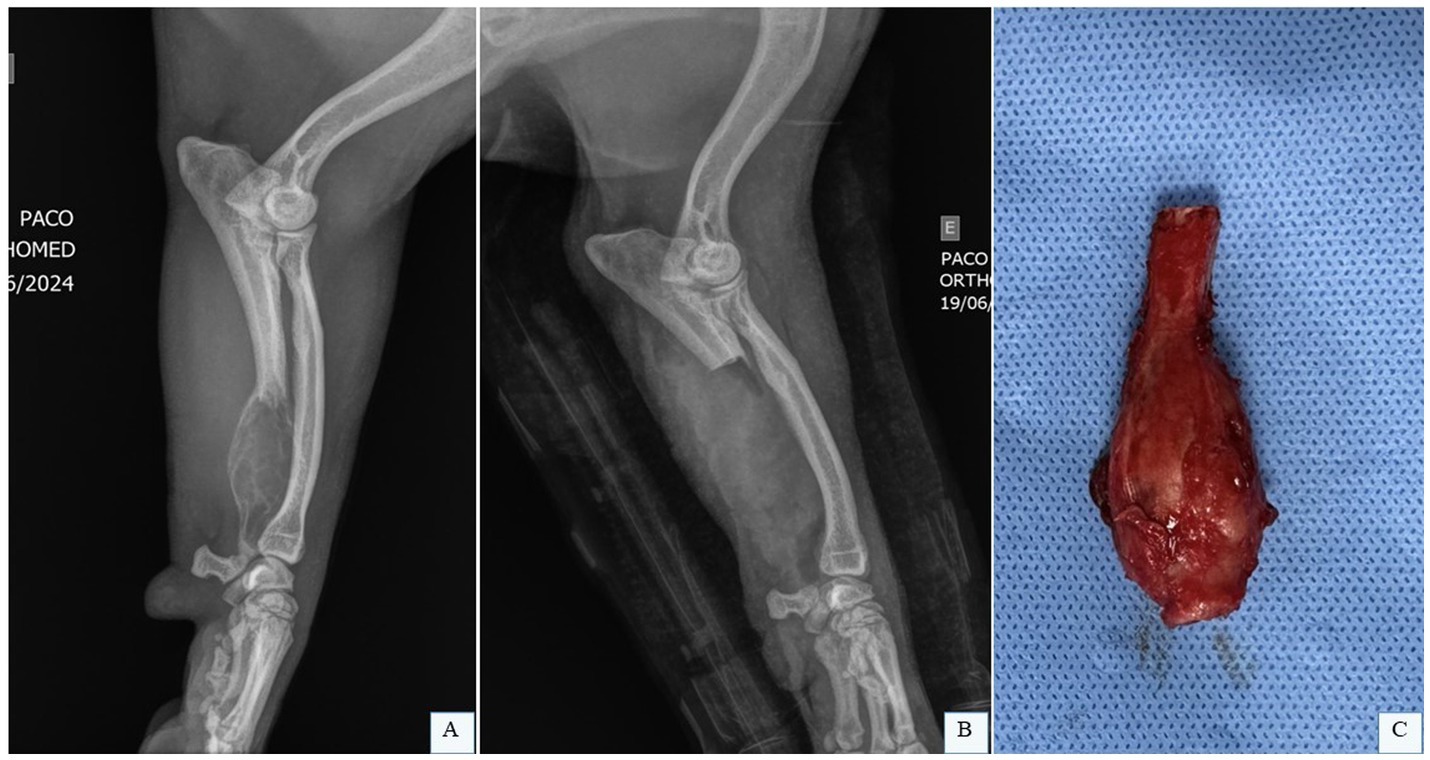

Pasteurization involves submerging the tumor-bearing bone in a sterile water bath at 65 °C for 40 min (11, 36), while liquid nitrogen protocols (Figure 6A) employ cycles of freezing at −196 °C for 20 min, thawing at 20 °C for 15 min, and incubation in saline at 30 °C for 10 min (38). Unlike autoclaving, which uses high heat, pasteurization and liquid nitrogen preserve bone morphogenetic proteins essential for healing, enhancing consolidation rates (11, 36, 37). Following tumor resection with adequate margins, soft tissues are removed, and the bone segment undergoes sterilization via the chosen method (Figure 6B). If arthrodesis is planned, joint preparation is completed during this phase. The treated bone is then reimplanted into the defect (Figure 6C) and secured with a bone plate, mirroring cortical allograft fixation techniques (15).

Figure 6

Panel A shows a bone being boiled in a metal pot. Panel B displays a close-up of the prepared bone on a blue surface. Panel C depicts the bone being used in a surgical procedure involving gloved hands.

Figure 6. Intraoperative bone allograft treatment. (A) Liquid nitrogen application. (B) Excised tumor-bearing bone segment treated with liquid nitrogen to eradicate neoplastic cells. (C) Treated bone segment repositioned into the surgical defect for plate fixation. Courtesy of Dr. Arthur Gouveia Rocha – Small Animal Surgery Service, Universidade Estadual Paulista (UNESP), Jaboticabal, Brazil; none of the images have been published in any other scientific work.

Yazawa et al. (37) reported three clinical cases of dogs with appendicular OSA in the thoracic limb. Surgical management involved liquid nitrogen treatment of the autologous bone followed by reconstruction. The affected sites included the left proximal scapula, right proximal humerus, and right distal radius. After tumor resection, soft tissues were excised, and the bone segment was treated with liquid nitrogen at −196 °C, thawed at room temperature, and incubated in saline before being reimplanted and fixed with orthopedic implants. The authors noted successful postoperative weight-bearing, ease of defect reconstruction, and a lower incidence of surgical site infections compared to other methods. The technique’s simplicity, requiring no specialized equipment, was emphasized as a key advantage. Yazawa et al. (37) considered that liquid nitrogen-treated autografts are a highly effective and promising alternative to thoracic limb amputation.